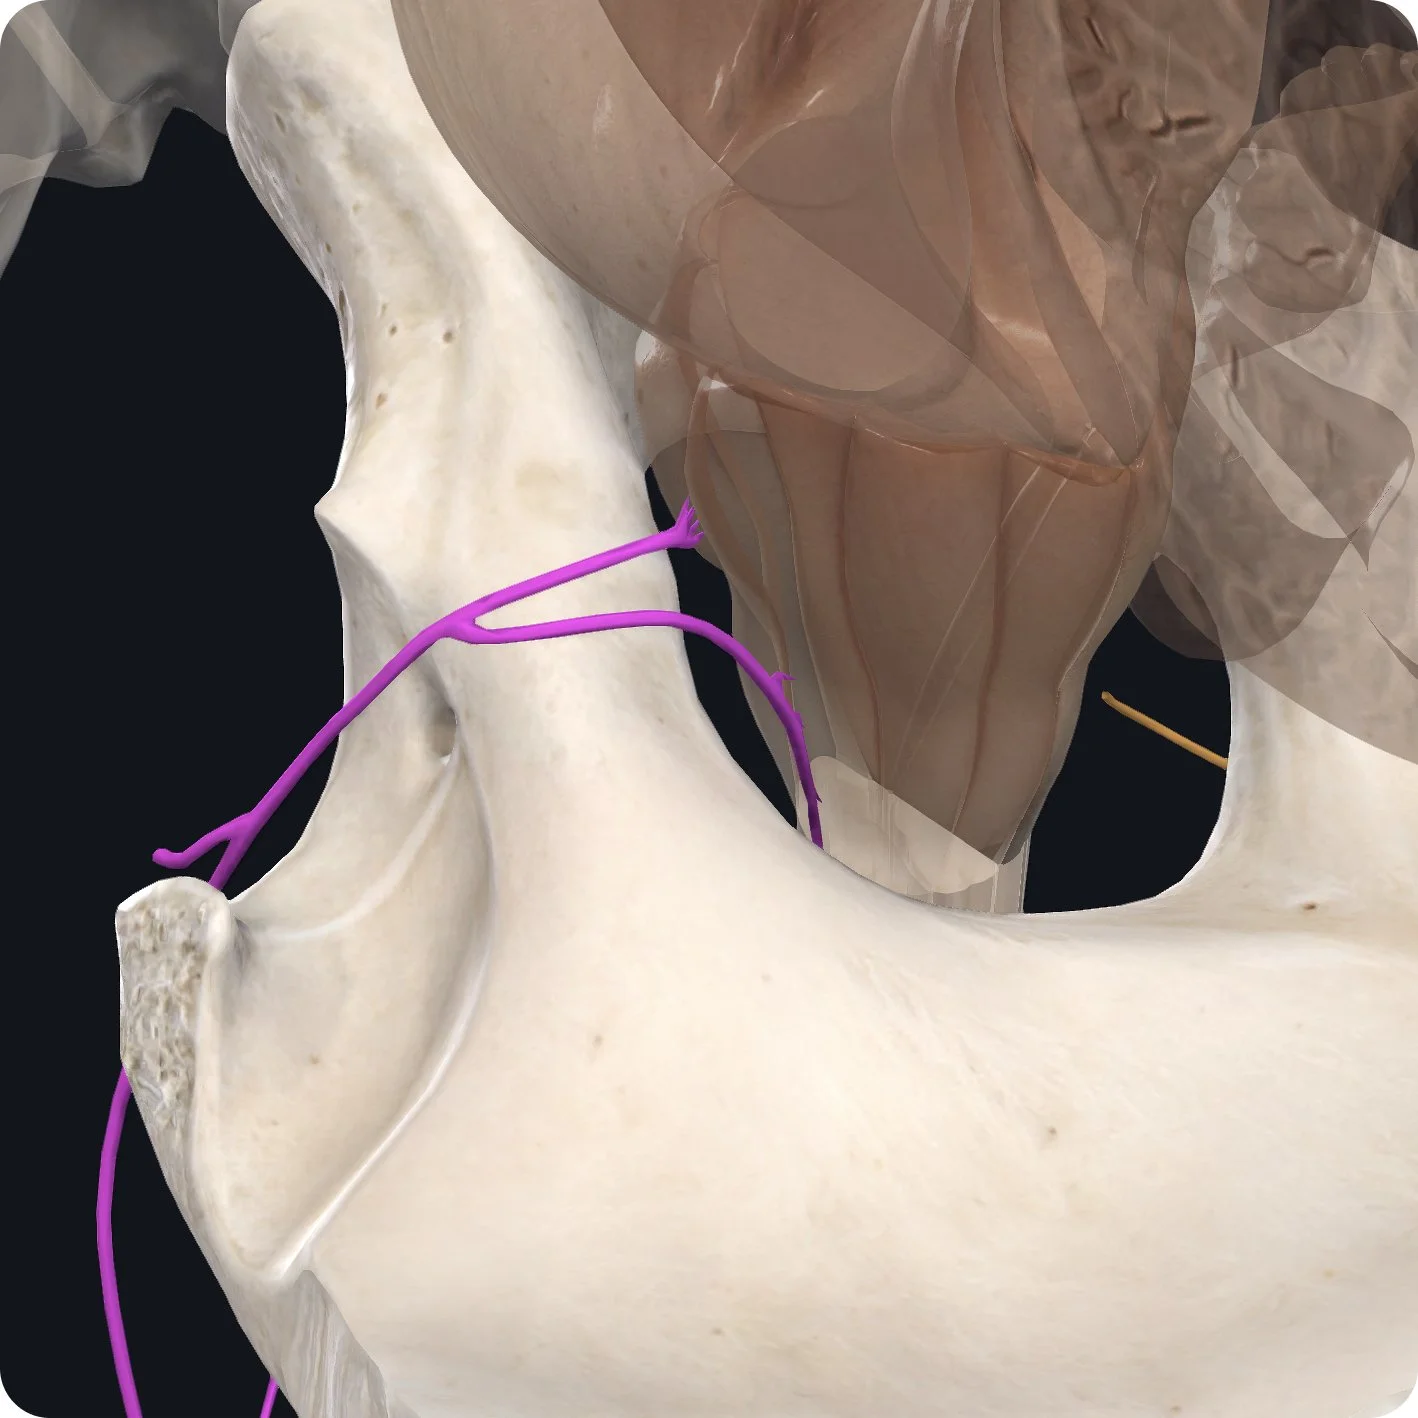

One of the most distinguishable cranial nerves, the accessory nerve arises from both the brainstem and the cervical spinal cord, located down in the cervical vertebrae.

The accessory nerve then ascends up through the foramen magnum.

It then traverses laterally through the posterior cranial fossa alongside cranial nerve ix, the glossopharyngeal nerve, and cranial nerve x, the vagus nerve.

It exits out the jugular foramen.

The accessory nerve then sends branches to two large muscles. First, the nerve innervates a large muscle in the front of our neck, the sternocleidomastoid muscle (SCM).

The SCM derives its name from its attachments; that is- the sternum and clavicle inferiorly, and the mastoid process of our temporal bone superiorly.

The SCM is responsible for cervical spinal flexion (tilting the head forward) as well as rotating the head and neck.